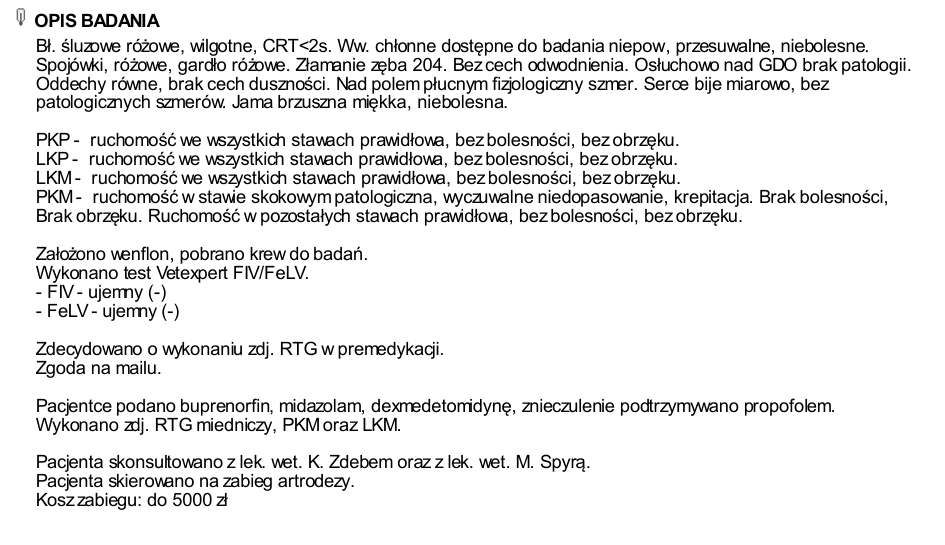

Wykonaliśmy malutkiej badania krwi, testy FIV/FELV. Koteczka ma trochę podwyższone leukocyty. Będziemy monitorować ten parametr.

Niestety problem z nóżką okazał się być o wiele bardziej poważny, niż "tylko" złamanie :-(.

Na najbliższy piątek, tj. 16 maja koteczka ma umówiony zabieg artrodezy,

Artrodeza jest zabiegiem operacyjnym trwale znoszącym ruchomość stawu. Artrodeza polega na usunięciu powierzchni stawowych i resekcji tkanki kostnej, a następnie stabilnemu zespoleniu kości tak, aby uległy trwałemu zrośnięciu.

Zebrana kwota będzie przeznaczona na:

- opłacenie zabiegu artrodezy (do 5 000 zł)

- opłacenie pierwszej wizyty Wojtusi u weta (w tym badanie krwi, testy FIV/FELV, zdjęcia RTG w sedacji - około 600 zł

- dodatkowej wizyty ortopedycznej, w tym wymiana opartrunku